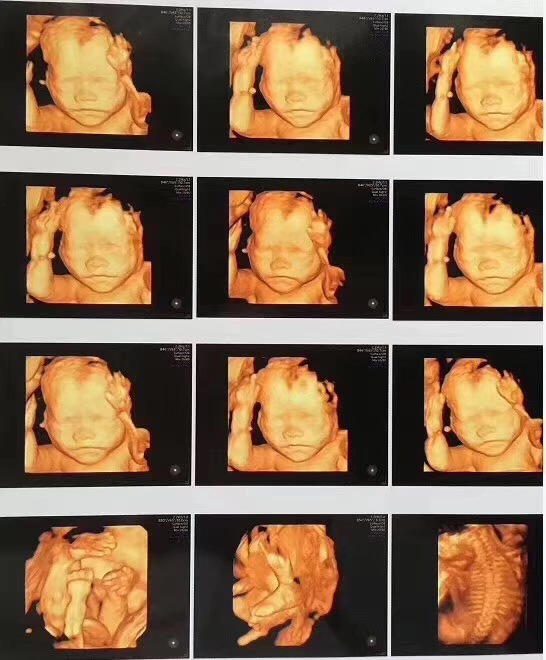

三、孕中期排除畸形检查

sw.jpg

孕中期开始,就可以通过四维彩超来观察胎儿的情况。通过宝宝的头部、四肢以及各种脏器的形状等发育情况来判断宝宝是否存在畸形。而对于这个检查,医生一般是建议在孕满24周之后,便可以开始检查了。这一次检查对于孕期来说,是非常重要的一次B超,是孕妈最不能缺少的一次。